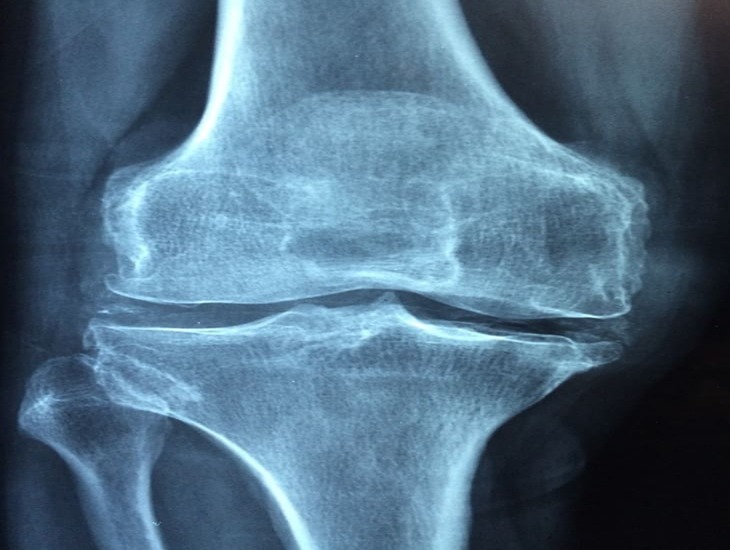

Благодаря вибрации можно восстановить здоровье коленей, об этом сообщили ученые по итогам обследования.

По итогам исследований удалось выяснить, что вибрационная терапия восстановила здоровье и убрала постоянную боль в коленях.